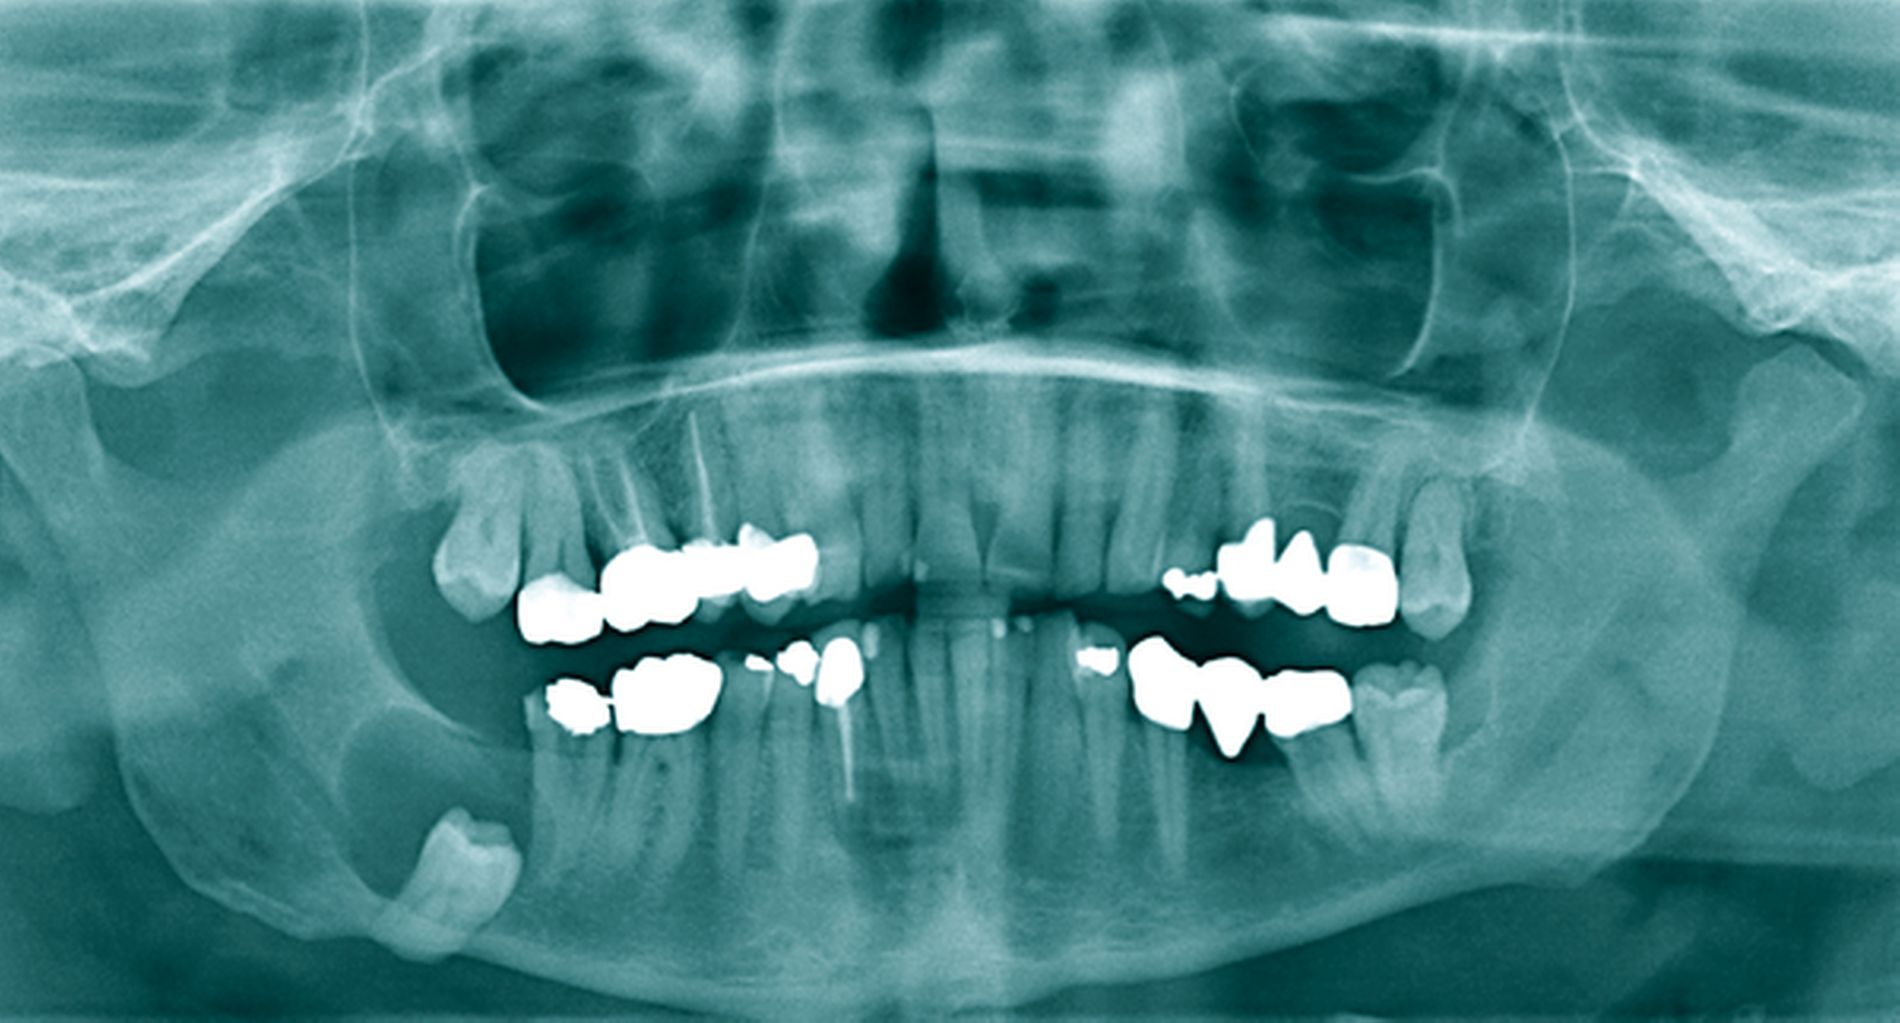

Ein 14-jähriger Patient wurde mit dem Zufallsbefund einer zystischen Raumforderung im Bereich des Kieferwinkels rechts in unser MVZ überwiesen (Abbildung 5a). Aufgrund der Ausdehnung mit Affektion des N. alveolaris inferior sowie der Wurzelspitzen der Zähne 47 und 46 wurde sich nach Abwägung der perioperativen Risiken in enger Absprache mit den Eltern und dem Patienten gegen eine primäre Zystektomie mit Entfernung des extrem verlagerten Zahnes 48 entschieden. Eltern und Patient bevorzugten – trotz absehbar längerer Behandlungszeit – die primäre Verkleinerung der Zyste mittels Obturatortherapie.

Das histopathologische Gutachten ergab die Diagnose einer Keratozyste. Daher erfolgte bereits nach drei Monaten eine Verlaufskontrolle mittels OPG, um ein Ansprechen auf die Therapie sicherzustellen. Nach sechs Monaten bereits war die Ausdehnung der Keratozyste so weit regredient, dass die vollständige Entfernung des Restbefunds sowie des Zahnes 48 mit risikoarmem Anfrischen des umliegenden Knochens in ambulanter ITN erfolgen konnte (Abbildung 5b). Die Zähne 18, 28 und 38 wurden dabei ebenfalls entfernt. Die Sensibilität der Unterlippe sowie der Zähne 46 und 47 konnte erhalten werden. Die Verlaufskontrolle nach einem weiteren halben Jahr zeigte eine gute knöcherne Durchbauung des ehemaligen Defekts im Bereich des Kieferwinkels rechts und der Patient blieb weiterhin beschwerdefrei (Abbildung 5c).